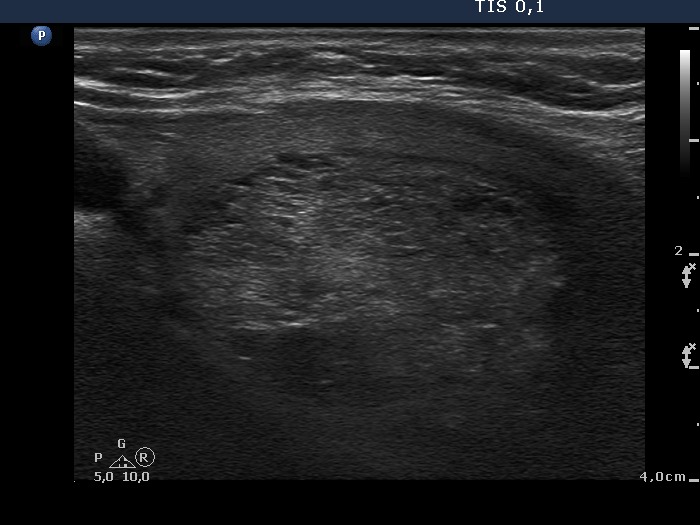

Ultrasonography: the thyroids were echonormal. There was a small hypoechogenic lesion in the ventral part of the right lobe, while a large hyperechogenic nodule presenting a halo sign and perinodular blood flow in the left thyroid. The size of the nodule increased from 25x19x27 mm to 30x27x33 mm (width, depth, length, respectively).

Histopathology disclosed follicular adenoma.